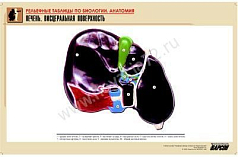

12. Печень. Висцеральная поверхность;